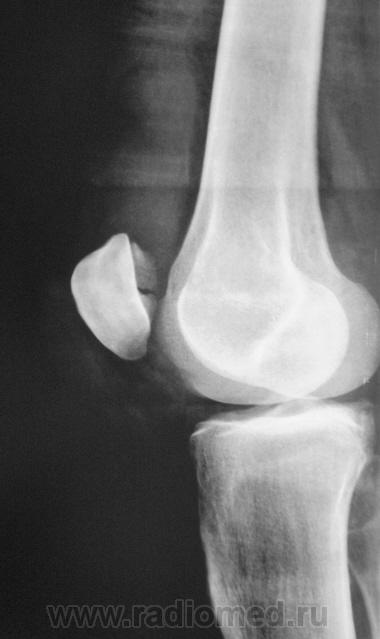

перелом надколенника( редко такой встречается) препателярная гемабурса, гемартроз, сильно пострадала суставная поверхность надколенника

Наверно все таки пателля бипартита. Представить, чтобы так красиво и ровно откололось - трудно... А мягкотканный компонент знатный...

Сам думал о "бипарцита", кстати, недавно был случай с "трипарцита". Но в данном случае был в растерянности, клиника "зашкаливает", конечно, возможно из-за мягкотканного компонента.

Кстати, на обычной рентгенограмме, произведенной в ургентных условиях "мягкотканный компонент" едва угадывается. Сильно "Сиар" спасает.

В минус травме говорит такая "красивенькая форма" отломка? НО при бипарите про мягкотканный компонент я данных ненашел..